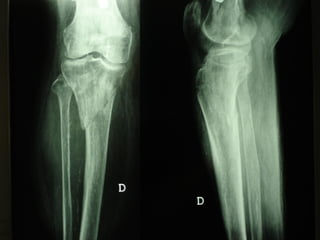

INDICAZIONI COMUNI Fratture sovracondiloidee Fratture intercondiliodee Fratture diafisarie distali PARTICOLARI Fratture con grave osteoporosi Fratture periprotesiche

VANTAGGI CHIRURGIA MININVASIVA Mini Open Inserimento della placca sottocutaneo per scivolamento Viti percutanee Preservazione dei tessuti molli Ridotto danno vascolare Rapida ripresa funzionale

F, 68 y

LISS  NCB

NCB

Conclusioni Riduzione  anatomica Minimo trauma chirurgico Corretto equilibrio fra elasticità e stabilità Precoce mobilizzazione